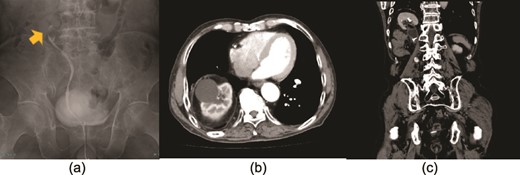

A 76-year-old man visited our hospital with a chief complaint of right upper quadrant abdominal pain. He had undergone low antegrade resection for rectal cancer and resection of liver metastases two decades previously. Computed tomography (CT) revealed pelvic dilatation with minor urinary extravasation in the tissue surrounding the right kidney, which was located in the thorax, with elevation of the diaphragm. He underwent retrograde pyelography, which showed a 3 cm filling defect in the upper ureter, suggesting ureteral cancer. A ureteral stent was placed simultaneously to relieve the symptoms. Urine cytology was positive for urothelial carcinoma, cystoscopy revealed no tumor in the bladder, and CT showed no signs of lymph node or distant metastasis. Ureteral carcinoma was diagnosed as cT2N0M0 (Fig. 1a). In addition, the affected ureter was associated with a thoracic kidney. The origin of the right renal artery and the entry of the renal vein were at the same level as those of the contralateral kidney (Fig. 1b). Shortly thereafter, the patient was referred to our department for surgery. Because the patient had a history of abdominal surgery, a retroperitoneal approach to radical nephroureterectomy was preferred. Renal vascular control was performed via the usual port placement. However, handling the suprahilar area and the superior aspect of the kidney was determined to be challenging due to cephalad deviation. Therefore, an additional intercostal trocar was planned after securing sufficient retroperitoneal space. In cases of insufficient retroperitoneal space for the trocar, a transthoracic approach via thoracoscopic surgery was prepared in collaboration with thoracic surgeons.

The yellow arrow in the retrograde pyelography shows a ureteral tumor in the upper ureter (a). There were no findings suggestive of metastases, and the clinical diagnosis was right ureteral carcinoma T2N0M0. An axial (b) and coronal (c) computed tomography view show the right kidney in the thorax with protrusion of the diaphragm, suggesting a thoracic kidney.